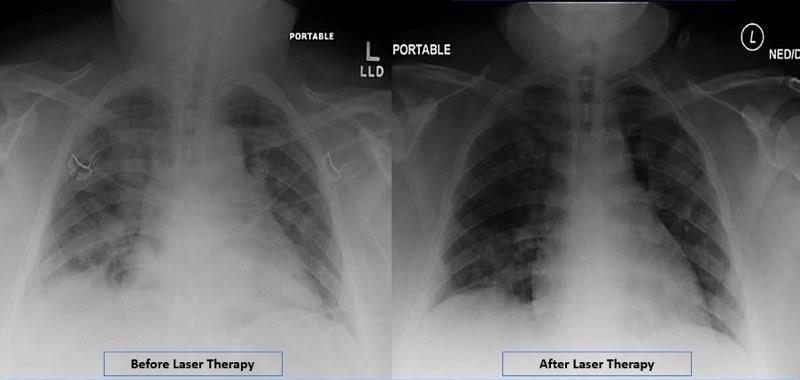

MLS® laserová terapie nově prokázala významné terapeutické účinky v rámci ošetření pacientů s intersticiální pneumonií způsobené COVID19 v Massachusets General Hospital , na jaře 2020.

Pacienti po jednotlivých ošetřeních vykazovali významné zlepšení kritických parametrů, jako je

saturace kyslíkem, zánětlivé markery...

Stejné účinky se v současnosti potvrzují na ostatních pracovištích, kde byl robotizovaný systém pro MLS ® Laserovou Terapii použit pro tuto indikaci.